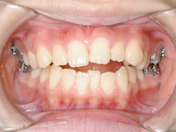

4) 治療に用いた装置 ストレートタイブマルチブラケットシステム(018x025スロット)

パラタルバー、前歯はセラミックブラケット

5) 抜歯 すべての智歯(親知らず)計4本

6) 治療期間 開始時から装置装着まで3か月、マルチブラケット期間1年6か月、保定期間4年